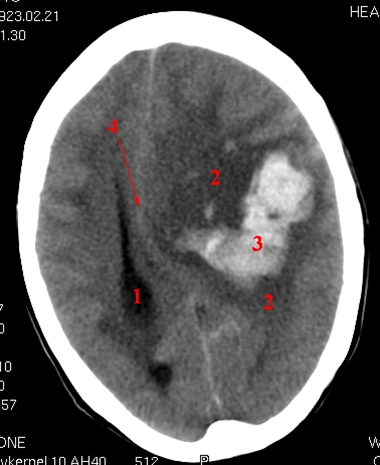

CT cerebrum uden kontrast.

Blødning (lyst område) i hjernen på patientens venstre side.

Betydeligt ødem (mørkt område) omkring blødningen (hæmatomet).

Venstre sideventrikel er komprimeret, og midtlinjestrukturerne er skubbet mod højre side.

1. Højre sideventrikel

2. Ødem

3. Blødning

4. Midtlinjestrukturer - falx cerebri